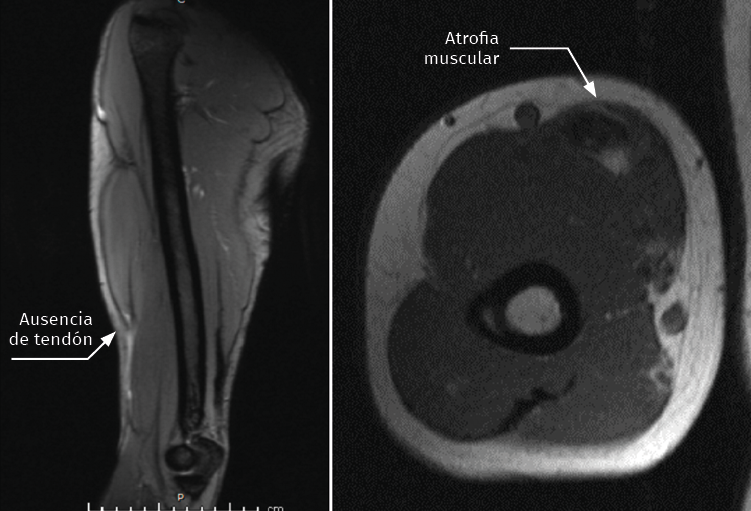

Se trata de un varón de 44 años con rotura del bíceps distal derecho de 6 meses de evolución, remitido para su valoración tras haber fracasado el tratamiento conservador que el paciente había decidido de forma voluntaria. A la exploración física, la movilidad del codo era completa pero manifestaba dolor en el vientre muscular a la contracción y un déficit de fuerza de flexión y pronosupinación que le impedía reincorporarse a su actividad laboral. Las pruebas diagnósticas preoperatorias como la resonancia magnética (RM) objetivaban la atrofia muscular, el ascenso y la casi ausencia completa de tendón bicipital (Figura 1).

Figura 1. Imagen de resonancia magnética preoperatoria. Se objetiva la atrofia muscular y la ausencia de cabo tendinoso.